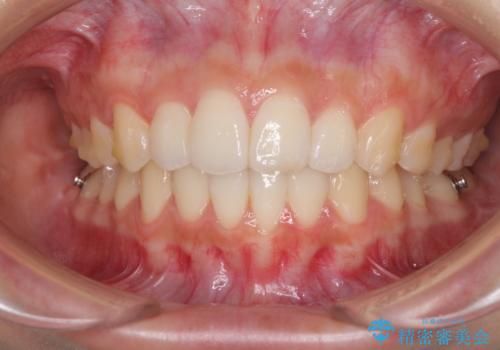

前歯のデコボコと突出感 インビザラインで改善

- 上下前歯のデコボコを気にして来院された患者様です。

インビザラインによる上下歯列の側方拡大と後方移動、IPR(歯と歯の間を削る)にるスペースの獲得により歯列を整えることとしました。

骨格的な左右差があったため、上下の正中を合わせることは困難かと思われましたが、何とか合わせることができました。

一方、骨格の差は改善できないため、奥歯の咬み合わせに物足りなさを感じました。

奥歯の咬み合わせによる不自由はなく、患者様に大変満足していただきました。